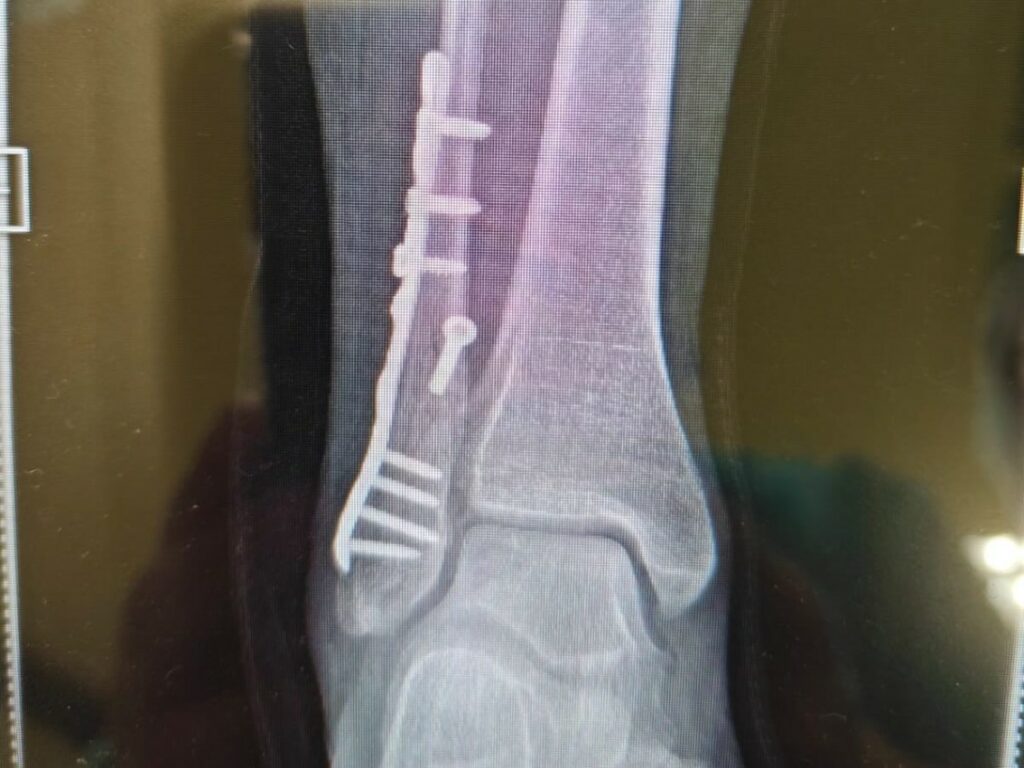

La brasiliana il 26 dicembre si era mostrata sul social col piede ingessato. “Era tutto troppo bello per essere vero. Ma neanche con la caviglia rotta perdo il sorriso!! Fortunata di avere accanto le persone che amo”. Non aveva spiegato come era accaduto il doloroso imprevisto, ma aveva mostrato la lastra che evidenziava la frattura.

A distanza di pochi giorni, l’ortopedico ha deciso di intervenire chirurgicamente. La 40enne sorride dopo l'intervento nel letto d’ospedale a Milano: ha con sé, come portafortuna, un orsetto di peluche. “Inizierò il mio anno così! Con il piede destro ‘bionico’! Oggi mi sono operata la frattura al malleolo peroneale, mi hanno messo una placca di titanio e delle viti. E’ andato tutto benissimo. Tra 20 giorni tornerò a camminare con un tutore che più sembra uno stivale di Louboutin! Nero, esagerato con la suola rossa”, scrive.